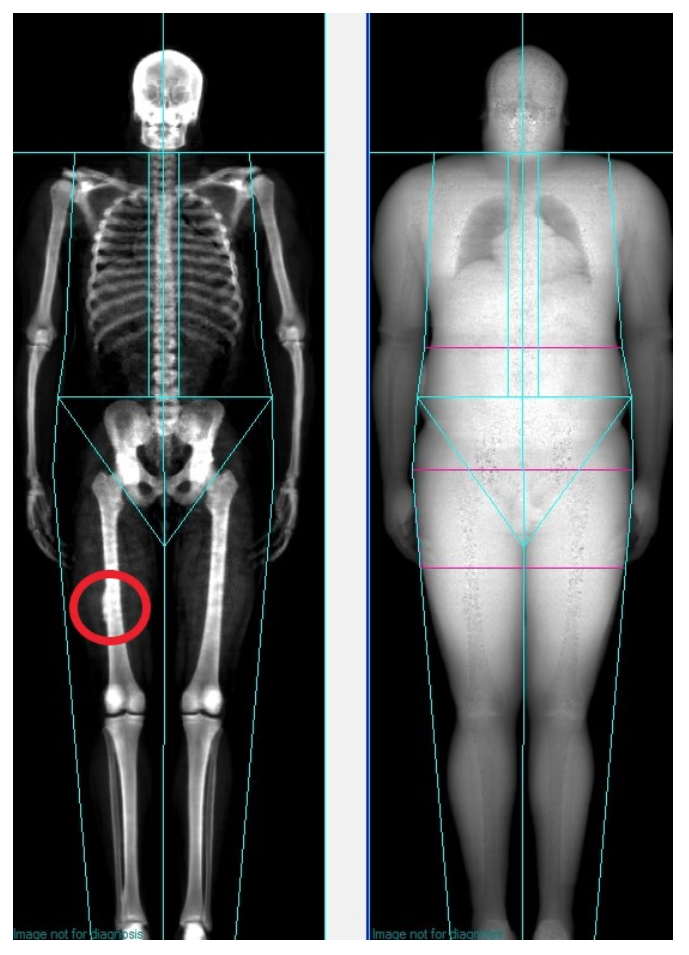

Since the NFL Football Combine just concluded a few weeks ago, I thought I would start with a scan that pertains to football. If you look at the scan below, you will notice on the subject’s right leg a little ghost (red circle) of an image on the femur. When I first saw this scan, I initially thought it was an artifact of some kind and did not pay any attention to it. However, on future scans of this individual, the artifact remained in exactly the same spot on every scan. Clearly, it was not an artifact, but something with the bone itself. In conversations with this individual, I found out that during his career he was on the kickoff team and he went downfield to tackle an individual who was running at full speed. The ball carrier lowered his head and his helmet struck this individual squarely in his thigh pad. The force that the ball carrier delivered with his helmet was enough to crack this individual’s thigh pad. Of course, he got a new thigh pad, but he also had a lot of pain in the area following the game. The team’s medical staff examined the leg and determined that this individual had suffered a bone contusion. The result of that bone contusion was that, over time, the spot on the femur that suffered the impact from the helmet calcified enough to create a visible “bump” on the DXA scan.

In examining the bone mineral content (BMC) between the right and left leg there was a small difference between the two legs (977 g vs. 974 g). However, this is not surprising being that the right leg was this individual’s dominant leg and there is often a little asymmetry between the two legs. The bone mineral density (BMD) for these two legs also demonstrated a similar result, with the BMD for these two legs being only slightly different (1.98 g/cm2) vs. 1.97 g/cm2).

Two things stick out for me regarding this scan. The first is that the DXA was able to pick up this small area of calcification. The second is how the force of one blow was enough to not just crack a thigh pad, but also, to alter the bone structure itself.